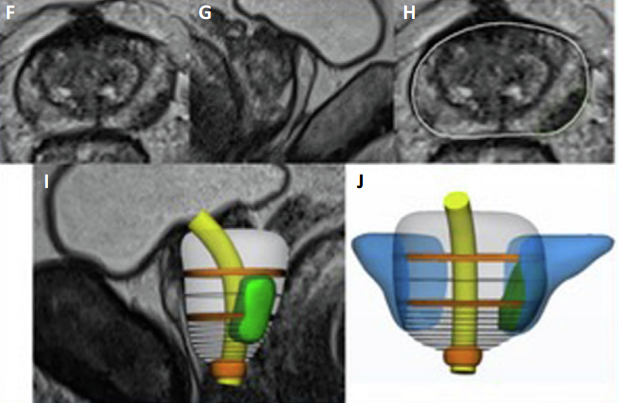

(F,G)前列腺的多参数磁共振成像(MRI)。 (H) 分割阶段以识别不同的解剖结构和病变位置及其包膜接触面。 (I)得到的3D模型可以叠加在MR图像上; 囊外延伸部分以浅绿色突出显示。 (J) 3D 虚拟模型可视化。

该3D影像可以上传到任何电子设备,如2D大屏、头戴式显示系统、机器人控制台等,以进行虚拟 3D 可视化,或者可以使用3D 打印机来打印 3D模型。如下图所示: